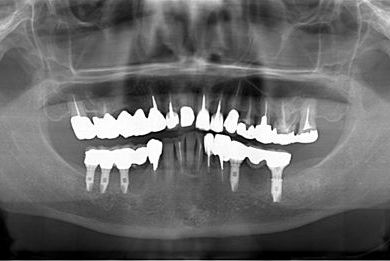

抜歯即日スピードインプラント治療+インプラント除去+セラミック治療

| 主訴 | 20年前に入れたインプラントの周囲が腫れて気になっている。左下の一部治療後の歯が欠けている。 | ||||||||||||||||||||||||||||||||

| 治療内容 | インプラント5本(抜歯即日スピードインプラント)、ハイブリッドセラミック9本(セラミック用土台2本)、メタルボンドセラミック2本(メタルボンド用土台1本)、インプラント除去1本 | ||||||||||||||||||||||||||||||||

| 総治療費 | 2,514,645円 | ||||||||||||||||||||||||||||||||

| 治療期間 | 1年11ヶ月 |